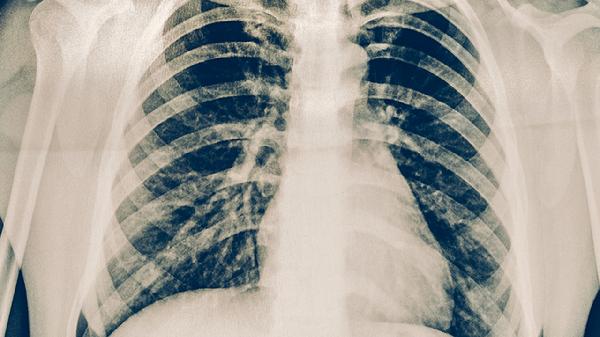

肺结核患者应遵医嘱完成6-8个月规范治疗,治疗期间保持均衡饮食,适当补充优质蛋白和维生素A/C/D。注意隔离防护,咳嗽时掩住口鼻,定期开窗通风。完成治疗后仍需定期复查胸部影像学,监测病情变化。